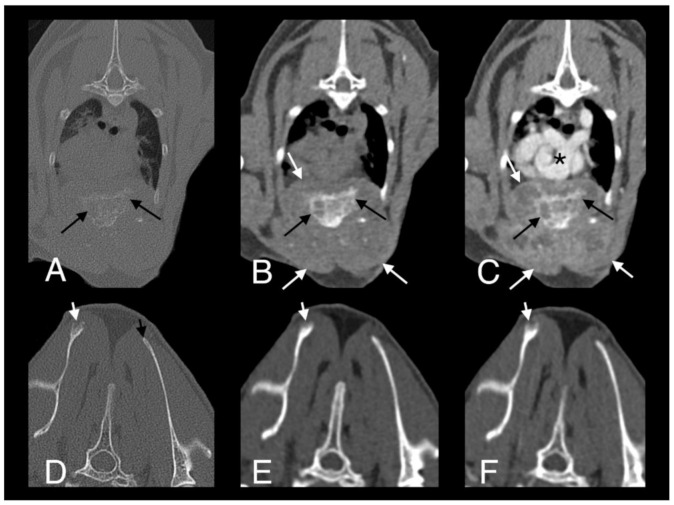

A full-body CT scan was performed. A large, poorly marginated, partially mineralized, and heterogeneously contrast-enhancing mass was identified along the pectoral region between the thoracic inlet and the sixth sternebra. Severe secondary osteolysis of sternebrae four and five was evident. The mass infiltrated the superficial and pectoral muscles bilaterally and extended dorsally within the thoracic cavity causing marked dorsal displacement of the heart and mild dorsal displacement of both cranial lung lobes (Figure 8A–C). A subtle lytic lesion was identified along the dorsal margin of the right scapula, with mildly contrast enhancing adjacent soft tissues (Figure 8D–F). Numerous well-marginated nodular soft tissue attenuating lesions, with associated heterogeneous contrast enhancement, were visible within the subcutaneous tissues of the ventral and dorsal thoracic wall. A generalized bronchial pattern was evident, with ill-defined areas of increased pulmonary attenuation, which was more pronounced in the cranial lung lobes. There was also regional lymphadenopathy.

Figure 8.

Computed tomography images in transverse plane of cat 2 with different reconstructions: bone (A,D), soft tissue (B,E), and soft tissue after contrast medium administration (C,F). Images A–C are at the level of the 4th and 5th sternebrae. There is a large, poorly marginated, partially mineralized and heterogeneously contrast enhancing mass infiltrating the adjacent pectoral musculature (white long arrows). Note severe secondary osteolysis of the sternebrae (black long arrows). Marked dorsal displacement of the heart is also visible (asterisk). Images D–F are at the level of the scapulae. Along the dorsal margin of the right scapula a subtle lytic lesion and mild contrast enhancement in the adjacent soft tissues are visible (short white arrows). The dorsal margin of the left scapula is normal (short black arrow).

Monitoring has continued. Four weeks later, the patient’s skin lesions had continued to improve. Repeated hematology and serum biochemistry were performed and there were no changes suggestive of hepatotoxicity secondary to rifampicin therapy, or neutropenia or thrombocytopenia secondary to pradofloxacin therapy. Fourteen weeks after starting triple antibiotic therapy, the skin lesions were almost completely healed and on a repeated full-body CT scan there was mild regression of the aggressive soft tissue mass infiltrating the pectoral muscles and resolution of the lytic lesion in the right scapula. However, there was only very mild improvement in the broncho-interstitial lung pattern. Daily treatment with rifampicin and azithromycin was continued but, on alternate days, the doses were doubled to 17.5 mg/kg PO and 15 mg/kg PO, respectively. Pradofloxacin was continued at the same dose and interval as before. A total of ten weeks later (24 weeks after starting treatment), the patient was tolerating the increased dose of rifampicin and azithromycin, and full-body CT showed further regression of the sternebral mass and moderate regression of the bronchial lung pattern. N-acetyl cysteine (NAC) (600 mg/cat PO q12 h; Essential Healthcare) was added to the treatment protocol to try to speed resolution due to its direct antimycobacterial effects as well as hepatoprotective activity [52,53]. The patient presented 21 weeks later (45 weeks after starting treatment) for repeated examinations. Hematology and serum biochemistry findings were unremarkable and full-body CT scan showed further improvement of the size and appearance of the sternebral mass and almost complete resolution of the pulmonary changes (Figure 9). There was moderate remodeling of the sternebrae, with much more solid bone present and no new osteolytic or proliferative changes. The soft tissue component of the lesion within the pectoral muscles was also markedly reduced in size and exhibited less contrast uptake. Antimicrobial therapy was ceased at this point, in part due to the cat becoming progressively reluctant to take oral medication. Careful monitoring of the patient has continued and there has been no evidence of relapse of active disease; a repeat CT scan three and a half months after stopping treatment showed minimal further change in the appearance of the lesions.

Figure 9.

Computed tomography images in transverse plane of cat 2 with different reconstructions: bone (A), soft tissue (B), and soft tissue after the administration of contrast medium (C). Images are at the level of the 4th and 5th sternebrae. Note moderate remodeling of the sternebrae with much more solid bone and no new osteolytic or proliferative changes (black arrows). The soft tissue component of the lesion within the pectoral muscles is markedly reduced in size and exhibits less contrast uptake (white arrows). Compare to Figure 8, images were taken at the same level.